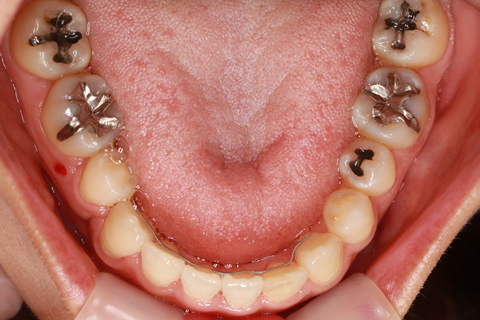

受け口(反対咬合)の症例

症例一覧